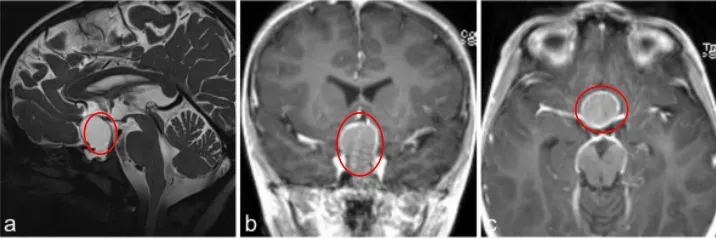

一名7岁的男童表现出垂体功能减退的症状,包括体重减轻、生长发育停滞、身体状况不佳以及疲劳感。在就诊前四周,他持续诉说头痛和呕吐,经过评估,被诊断为全垂体功能减退。

a–c图MR成像显示囊性病变对比增强,高度怀疑颅咽管瘤